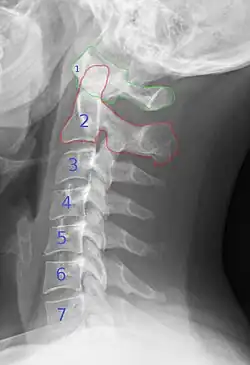

Halswirbelsäule

Die Halswirbelsäule (abgekürzt HWS) enthält die Wirbel zwischen Kopf und Brustwirbelsäule bei Menschen und den anderen Wirbeltieren.

Die Halswirbelsäule ist in der Regel der beweglichste Wirbelsäulenabschnitt. Die beiden dem Schädel am nächsten liegenden Wirbel haben Eigennamen: Atlas („Nicker“) und der Axis („Dreher“), bedingt durch ihre vom üblichen Aufbau eines Wirbels abweichende Bauform. Dieser obere Teil der Halswirbelsäule samt der Schädelbasis bildet die Kopfgelenke. Es folgen fünf weitere Halswirbel. Die Halswirbelsäule weist beim gesunden Menschen einen Bogen nach vorn auf, was als physiologische Lordose bezeichnet wird.

Beim Menschen liegt direkt unter dem Foramen magnum des Schädels der erste Halswirbel, der Atlas. Dieser ist nach Atlas aus der griechischen Mythologie benannt. Der Atlas trägt den Schädel und umfasst dabei den Zahn des zweiten Halswirbels, des Drehers (lat. Axis). Die Gelenke zwischen Schädelbasis und Axis bilden zusammen zwei Kopfgelenke, welche etwa 70 % der Beweglichkeit des Kopfes im Verhältnis zum Rumpf gewährleisten.

Die weiteren Halswirbel haben die übliche Form eines Wirbels mit dem Wirbelkörper und dem das Rückenmark umfassenden Wirbelbogen, an dessen seitlichen Fortsätzen sich jeweils rechts und links des Wirbelkanals die Wirbelbogengelenke oder auch Facettengelenke befinden.

Der 7. Halswirbel der menschlichen Wirbelsäule wird als Vertebra prominens (vorstehender Wirbel) bezeichnet, weil sein Dornfortsatz etwas weiter nach hinten vorsteht als der der anderen sechs Halswirbel. Daher ist der Dornfortsatz des 7. Halswirbels von außen am unteren Ende der Nackenfurche meist gut zu tasten und dient als anatomischer Orientierungspunkt.